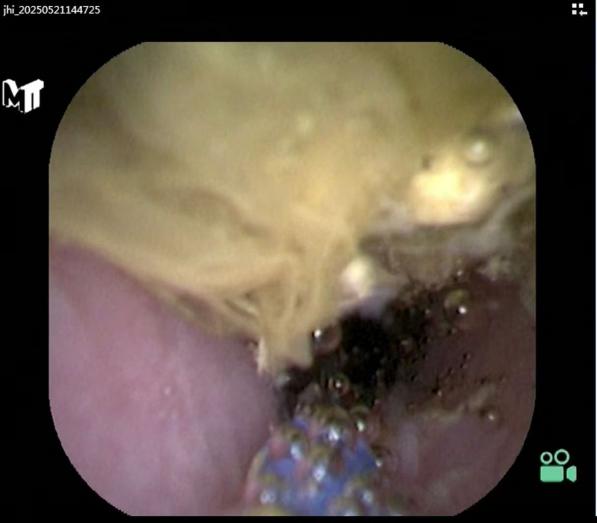

内镜下阑尾灌洗术:确认粪石阻塞是主因后,医生通过导管向阑尾腔内注入生理盐水或其他冲洗液。强大的水流冲击力旨在:冲走脓液和炎性渗出物,以迅速减轻腔内压力和炎症。

松动并冲出阻塞的粪石,以解除阑尾腔的梗阻,恢复其通畅性,这是炎症消退的关键。

内镜下阑尾取粪石术:如果灌洗无法冲出较大或嵌顿牢固的粪石,医生会使用内镜器械(如取石网篮、取石球囊),直接伸入阑尾腔内,精准抓取或套取粪石,从阑尾管腔取出,彻底解除梗阻。

对于脓液较多的严重病例,医生可能放置一根细小的塑料支架(引流管)在阑尾腔内,一端留在肠腔,持续引流几天,帮助炎症更快消退。